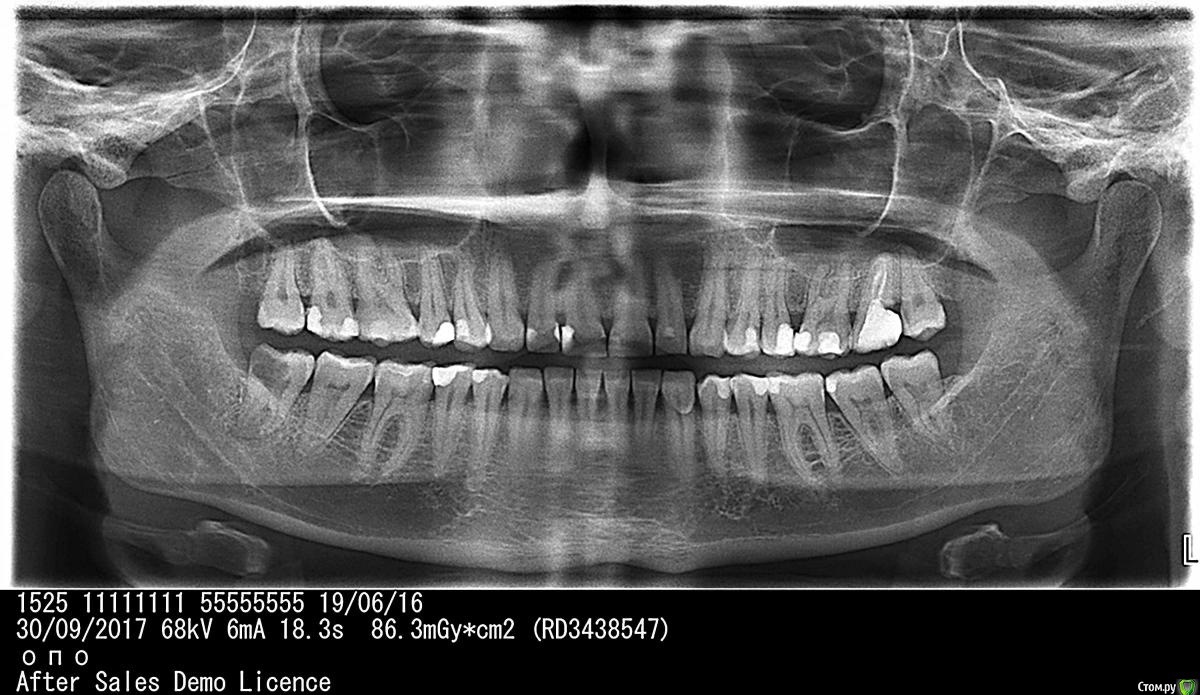

quint4me Опубликовано 1 октября, 2017 Поделиться Опубликовано 1 октября, 2017 (изменено) Добрый вечер! Скажите, пожалуйста, в каком состоянии находится 8-ка справа? Есть ли пульпит? Кариес? Какое лечение посоветуете? А так же, как обстоят дела с 7-кой слева? нужно ли удалять зуб? Изменено 1 октября, 2017 пользователем quint4me Ссылка на комментарий

red_butler Опубликовано 1 октября, 2017 Поделиться Опубликовано 1 октября, 2017 мудрый и 2.7 удалять Ссылка на комментарий

IvanK Опубликовано 2 октября, 2017 Поделиться Опубликовано 2 октября, 2017 мудрый и 2.7 удалять+1 +обратить внимание на контактные пункты 18-17, 14-15, 12-11, 25-26, Ссылка на комментарий